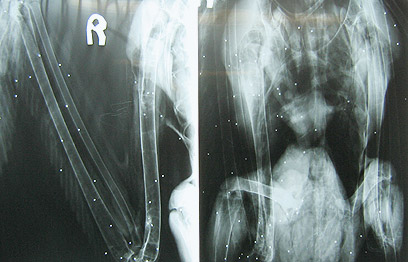

אוהד הצופה, אקולוג העופות של רשות הטבע והגנים, הגיע לאסוף את השקנאי הפצוע. "השקנאי הגיע עם דימומים ופגיעה בכנף הימנית. לאחר בדיקות רפואיות גילינו כי הוא ירוי ביותר ממאה כדוריות עופרת וכנראה נורה ברובה ציד. הרסיסים היו מפוזרים ברקמות השונות בגוף, אך למזלו הטוב, הם לא פגעו בכלי דם ראשי או באיבר חיוני", מגלה הצופה ל-ynet. "רוב השקנאים שנמצאים ירויים, לא זוכים למזל שכזה".

יותר מ-100 כדוריות עופרת נתגלו בגופו של השקנאי הפצוע (צילום: אוהד הצופה, רשות הטבע והגנים)